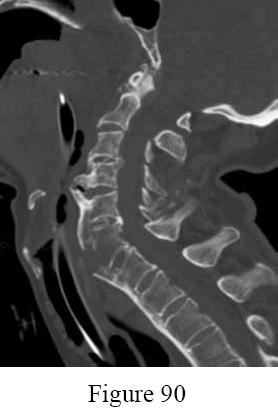

Question 16:

A 52-year-old man presents with sharp neck pain radiating down his right arm. Physical examination reveals weakness in active elbow extension and wrist flexion. He also reports decreased sensation isolated to the dorsum of his middle finger. Which cervical nerve root is most likely compressed?

Correct Answer: C7

Explanation:

Compression of the C7 nerve root causes a classic radiculopathy characterized by weakness in elbow extension (triceps) and wrist flexion (flexor carpi radialis), an absent or diminished triceps reflex, and sensory changes involving the middle finger. C6 radiculopathy typically involves wrist extension weakness and numbness in the thumb and index finger. C8 involves finger flexion and numbness in the small finger.